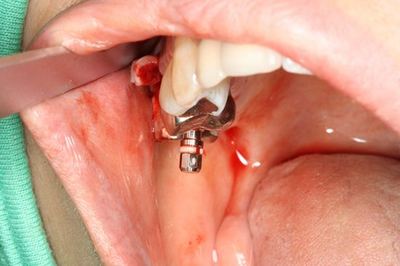

ミラー像

前後の金属も今後除去していきます。

![]()

ドリルガイドの適合を確認します。